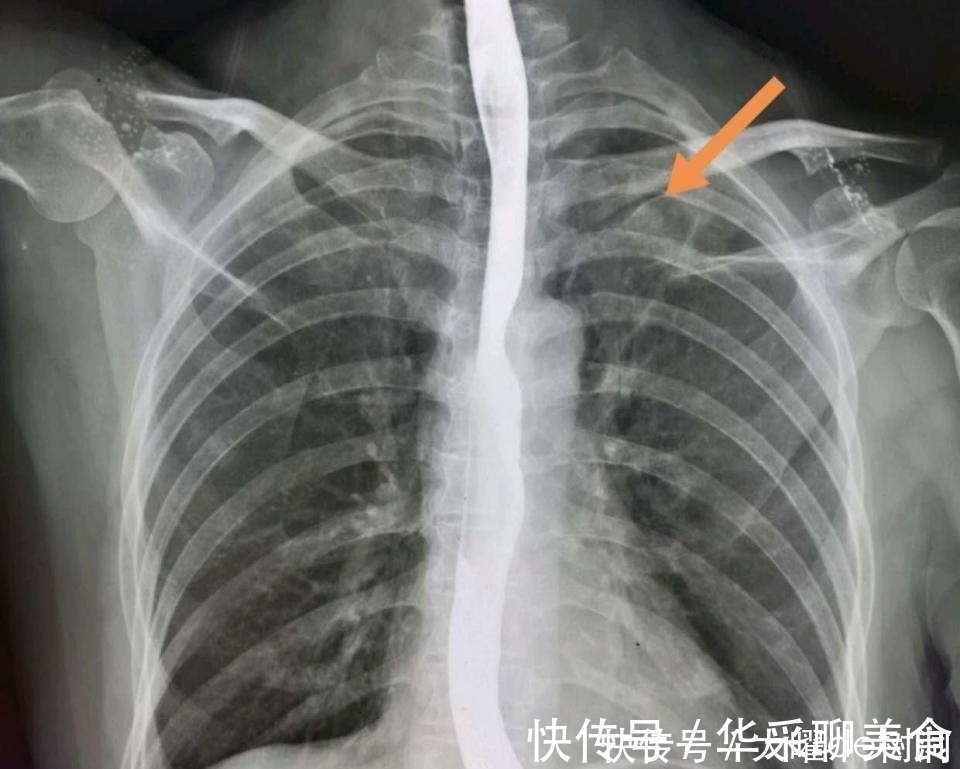

举个例子:很多单位的年度体检,肺部会选择胸片而不是胸部CT。

而胸部透视、胸片对早期肺癌的漏诊率很高。

文章插图

像上图这种小肺癌,胸片漏诊率几乎是100%的,但CT可以筛查出来,早期治愈。